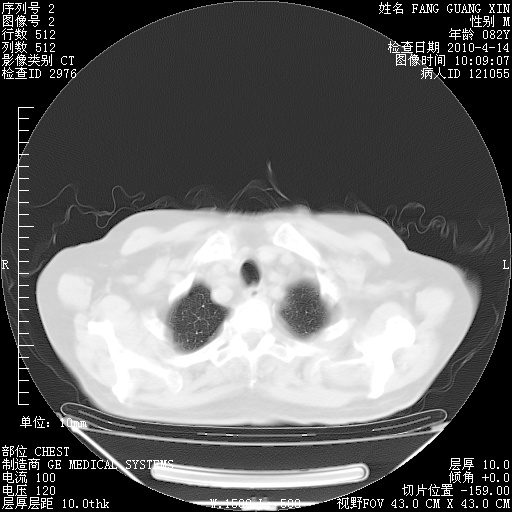

肺部CT平扫未见异常。